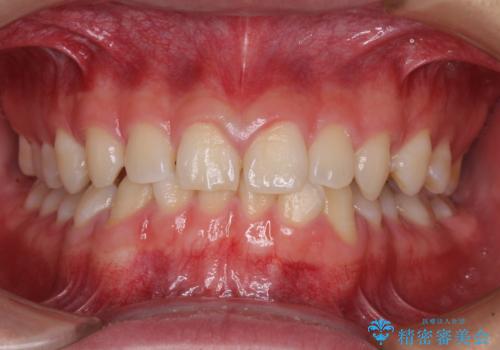

【インビザライン】マウスピース矯正希望。

担当医 河口智英